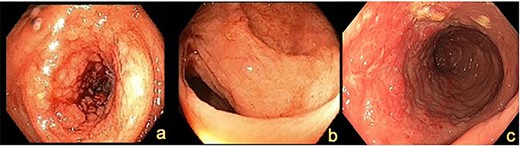

A 72-year-old female presented with abdominal pain and loss of weight. Computed tomography (CT) imaging demonstrated caecal and ascending colon thickening (Fig. 1a). Colonoscopy showed abnormal mucosa in the ascending colon that was unable to be traversed endoscopically (Fig. 2a) and slightly irregular mucosa at the hepatic flexure (Fig. 2b). The appearances were not typical of either a primary colon malignancy or a stricture secondary to inflammatory bowel disease (IBD). Biopsies were non-diagnostic, only showing mucosa with features of regeneration and repair. Given the patient was symptomatic, a laparoscopic right hemicolectomy was performed. Intraoperatively, a thickened firm ascending colon was seen suggesting possible submucosal involvement. Firm nodules were found in the terminal ileum mesentery and proximal transverse colon.

Colonoscopy demonstrating (a) ascending colon lesion, (b) hepatic flexure mucosal abnormality and (c) cobblestoned mucosa in the transverse colon.